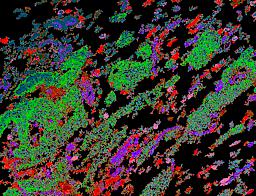

Pancreatic ductal adenocarcinoma is a lethal disease with limited treatment options and poor survival. We studied 83 spatial samples from 31 patients (11 treatment-naïve and 20 treated) using single-cell/nucleus RNA sequencing, bulk-proteogenomics, spatial transcriptomics and cellular imaging. Subpopulations of tumor cells exhibited signatures of proliferation, KRAS signaling, cell stress and epithelial-to-mesenchymal transition. Mapping mutations and copy number events distinguished tumor populations from normal and transitional cells, including acinar-to-ductal metaplasia and pancreatic intraepithelial neoplasia. Pathology-assisted deconvolution of spatial transcriptomic data identified tumor and transitional subpopulations with distinct histological features. We showed coordinated expression of TIGIT in exhausted and regulatory T cells and Nectin in tumor cells. Chemo-resistant samples contain a threefold enrichment of inflammatory cancer-associated fibroblasts that upregulate metallothioneins. Our study reveals a deeper understanding of the intricate substructure of pancreatic ductal adenocarcinoma tumors that could help improve therapy for patients with this disease.